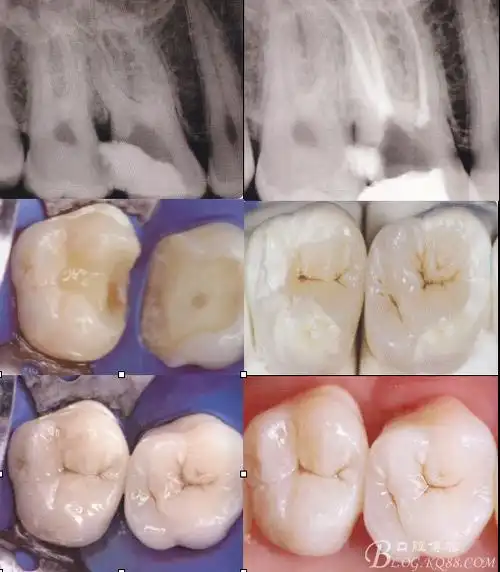

根管再治疗 美塑树脂嵌体修复1例

根管治疗后微创修复嵌体高嵌体